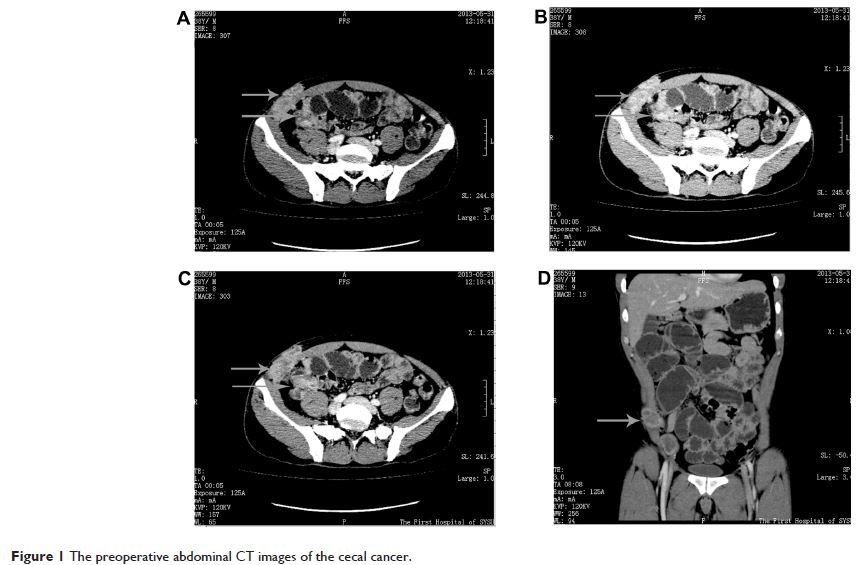

无张力修补术在盲肠癌并腹壁、腹股沟淋巴结转移患者扩大根治术中的应用

论文中介绍了一例盲肠癌并腹壁、右腹股沟淋巴结转移,接受盲肠癌扩大根治术+右侧腹壁缺损无张力修补术(GORE® DUALMESH®)的病例。患者手术顺利,术中出血量约 200ml,生命体征平稳;术后诊断:盲肠中-低分化腺癌并腹壁、腹股沟淋巴结转移(pT4bN2bM1, IV4a);患者术后恢复可。